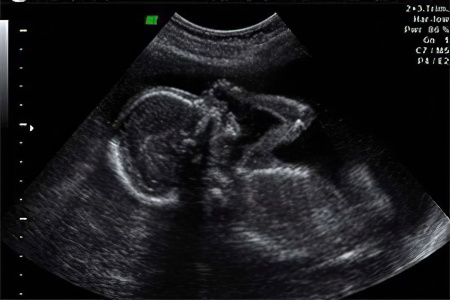

Второе плановое ультразвуковое исследование обычно проводится с 20 по 24 недели беременности. Однако в некоторых случаях, исходя из медицинских показаний, его могут назначить на 1-2 недели раньше. Основная задача этого исследования — оценка развития плода, состояния плаценты и матки. Если есть подозрения на генетические или хромосомные аномалии, специалист анализирует размер носового хряща и параметры воротниковой зоны плода.

Во время УЗИ можно выяснить:

- Состояние миометрия (мышечного слоя матки);

- Положение плаценты и риск предлежания;

- Состояние и объем амниотической жидкости;

- Соотношение размеров матки и плода;

- Оценка состояния внутренних органов и сердцебиения ребенка;

- Пол будущего малыша.

У плода уже формируется режим сна и бодрствования, поэтому во время исследования можно увидеть его в состоянии покоя или активно двигающимся в околоплодных водах.